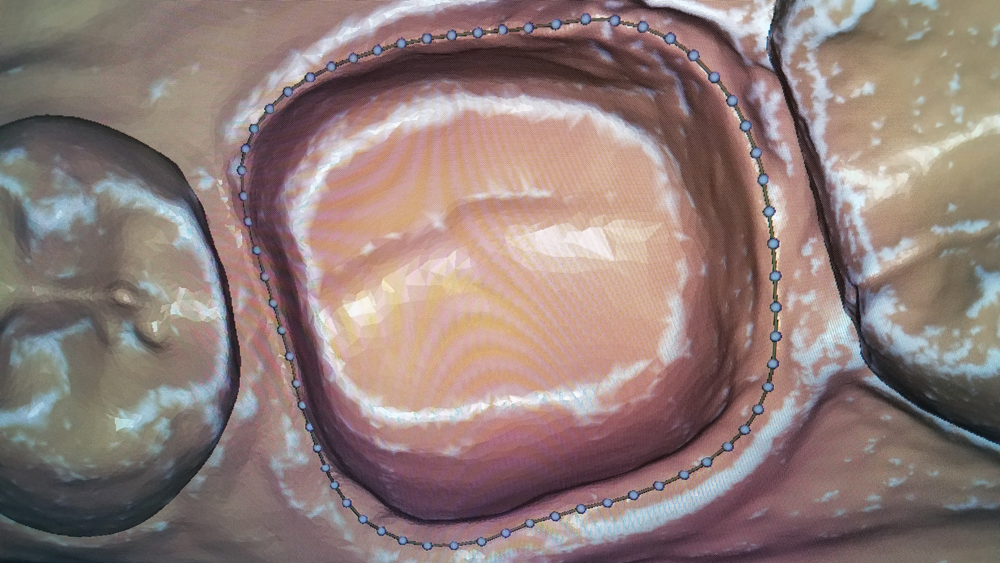

CASE REPORT

The following case highlights the efficient, user-friendly scanning capabilities of the iTero Element scanner, as well as the clinical advantages of connecting to the glidewell.io In-Office Solution for single-appointment dental restorations. The patient sought treatment for a damaged mandibular first molar with a cusp fracture. Because the case called for a single crown and high-strength zirconia, the patient was an ideal candidate for a same-visit restoration milled from a BruxZir NOW milling block. After preparing the tooth and taking an intraoral scan, the crown was fabricated within 40 minutes using the fastmill.io In-Office Unit. The final restoration fit perfectly without adjustment and exceeded the expectations of the patient, who was thrilled that she didn’t have to schedule a second appointment for the crown delivery.